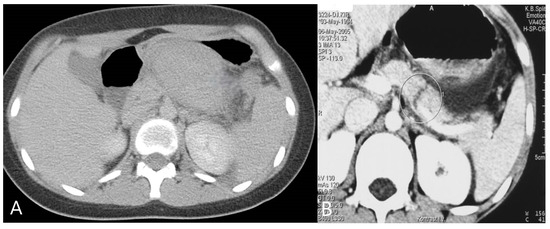

4. Spleen Injury

8.1. Kidney Injury